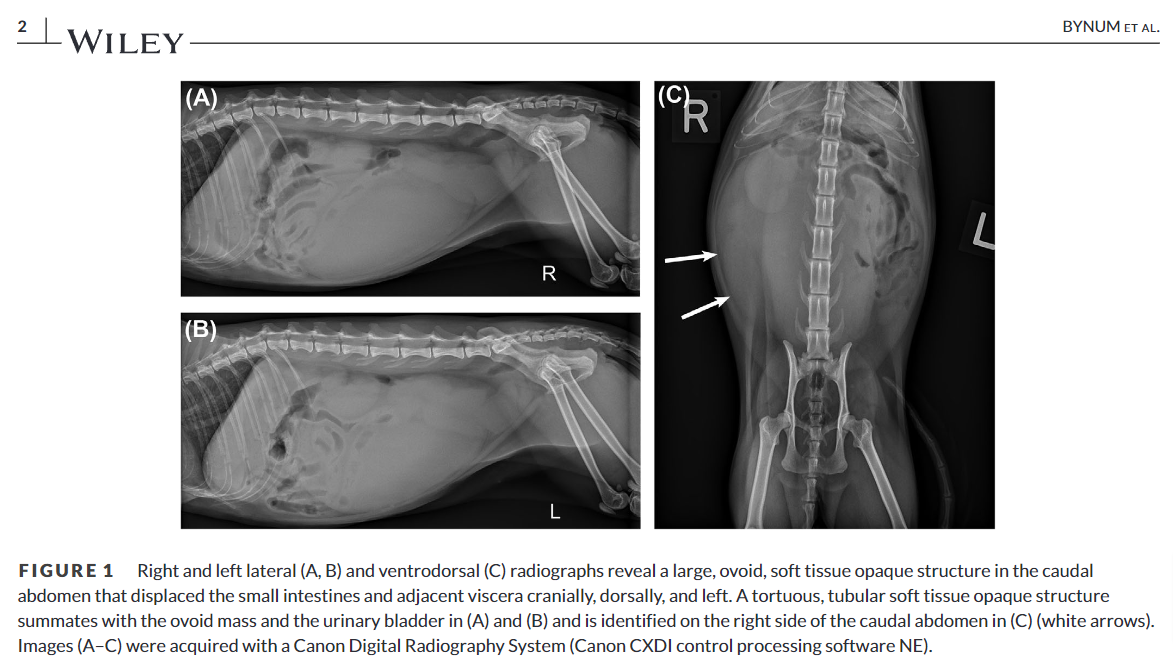

방사선 사진처럼 자궁염전이 발생하면 실제로 대형의 종괴성 병변으로 보이고 초음파 검사에서 cyst 양상으로 보인다. 이번 논문에서는 doppler 사진을 첨부하지 않아 검사의 완결성이 아쉬웠다.